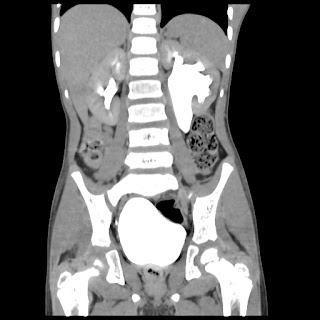

A 07 years old child with left side of abdomen pain

current CT images: